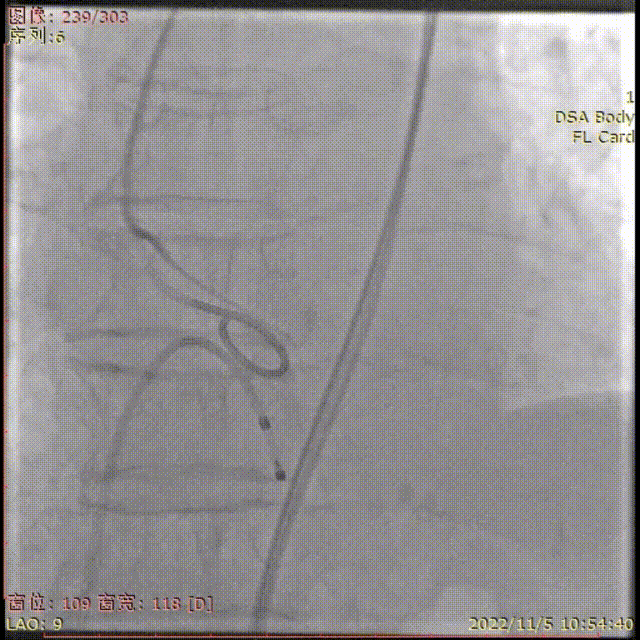

TaurusElite输送器顺利过弓

瓣膜初始定位

瓣膜稳定释放到工作位,无位移

工作位多角度评估